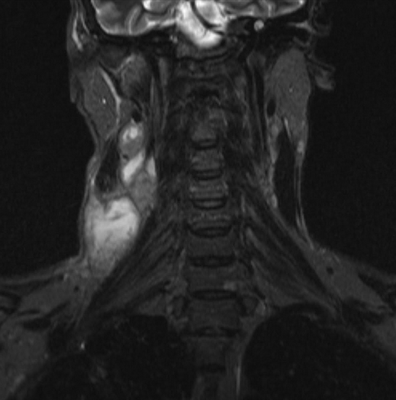

Результат МР-сканирования мягких тканей шеи

Туберкулезный лимфаденит на снимке МРТ

При исследовании шеи особое значение имеет сканирование гортани. Это сложный орган, в состав которого входят костные и хрящевые элементы, мышечная ткань, связочный аппарат. Частая локализация опухолей в области гортани является одной из причин тщательного обследования данной зоны.

При КТ гортани оценивают размер, границы, структуру подъязычной кости, надгортанника, щитовидного и черпаловидного хрящей, состояние трахеи.

МРТ информативнее при изучении состояния связок и мышц органа, выявляет

патологические процессы (воспалительные, неопластические), определяет локализацию поражения.